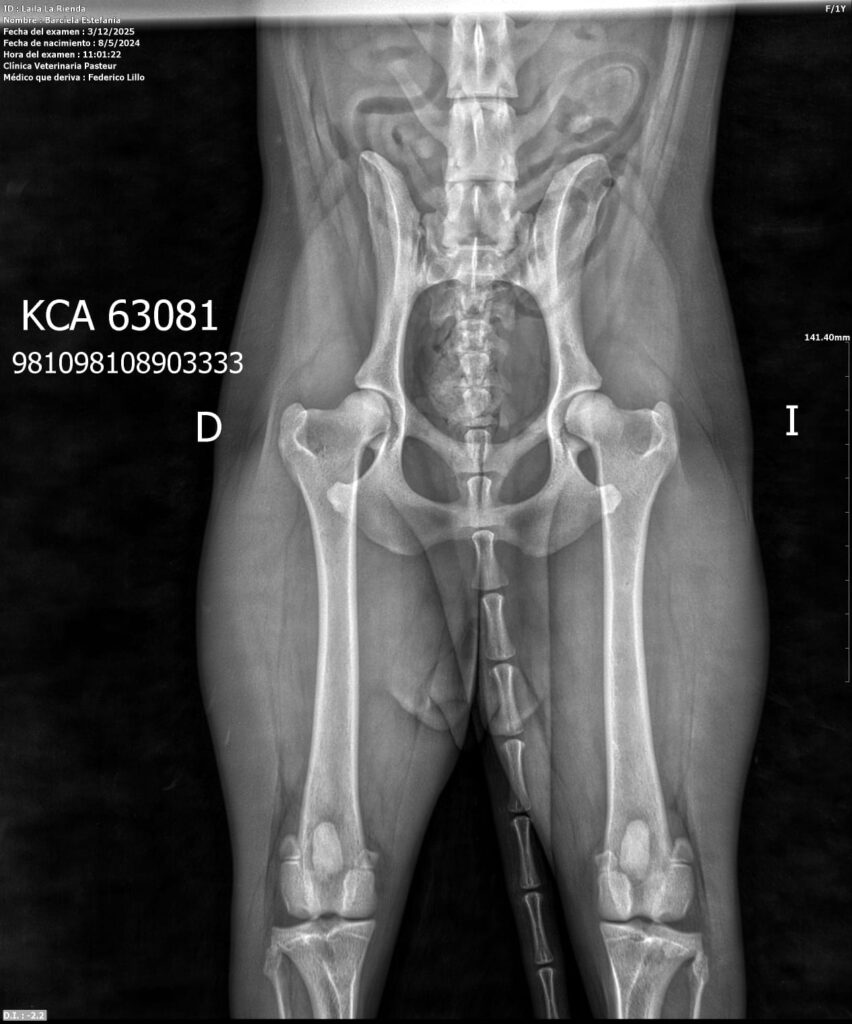

Placas de caderas y codos en La Rienda Border Collie

Realizamos radiografías oficiales de caderas y codos a nuestros reproductores, evaluadas por profesionales veterinarios especializados.

Estos estudios permiten detectar posibles patologías hereditarias, como la displasia de cadera y de codo, ayudando a reducir su incidencia generación tras generación.

✔ Clasificación A en caderas y codos, indicativo de articulaciones sanas y excelente conformación

✔ Clasificación A en codos y B en caderas, siempre informada con total transparencia y criterio de selección responsable